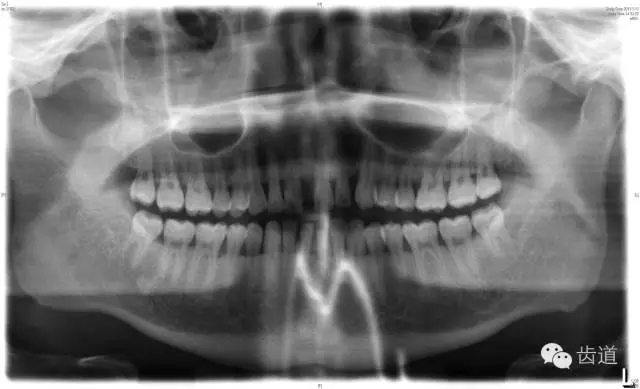

6、輔助檢查

X線:根尖片、曲面斷層片(牙槽嵴頂,水平垂直吸收,程度)

21.webp.jpg

22.webp.jpg

23.webp.jpg